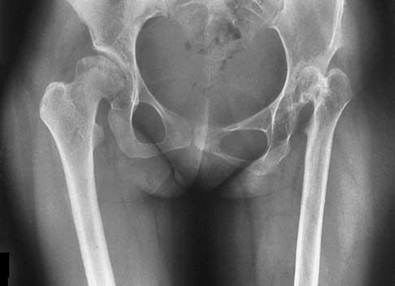

Figure 10 is an anteroposterior pelvis radiograph of an 82-year-old man who had right hip pain that began 2 weeks ago but has since resolved with use of over-the-counter nonsteroidal anti-inflammatory drugs (NSAIDs). Currently he has no pain. Examination of his hip shows decreased internal rotation and minimal pain at the extremes of motion. What is the most appropriate treatment at this point?

13

The radiograph shown is consistent with Paget disease of the bone. It demonstrates classic findings of widened lamellae and disorganized sclerotic and lytic areas. The cause is not clearly defined, but may be linked to a viral infection and subsequent alterations of osteoblastic and osteoclastic activity. Most patients are asymptomatic, and Paget disease is often found incidentally on radiographs. In this case, the patient’s symptoms likely were caused by hip arthritis, but Paget disease can cause diffuse bone pain in some cases. Considering the patient’s mild and short-term symptoms, observation and NSAID use is most appropriate. An MRI scan or biopsy is indicated if sarcomatous transformation is suspected, but this condition is rare and is associated with a substantial, unrelenting increase in pain. SPEP and UPEP are tests for multiple myeloma, of which the radiographs show no signs.